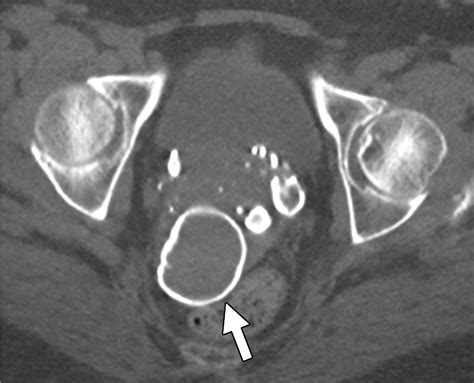

• Abdominal/Hepatic Calcifications: These are often found in the liver or peritoneum. They can sometimes be associated with previous infections, such as those caused by viruses (e.g., cytomegalovirus or toxoplasmosis) that have since resolved.

Abdominal/Liver May be related to past resolved infections or Meconium peritonitis.